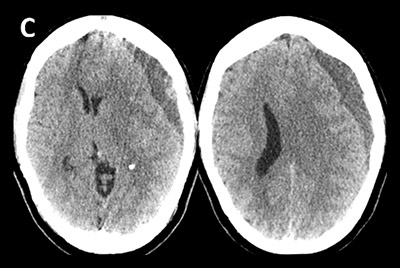

Reconstructed angiograms of a patient who received embolization of the middle meningeal artery; before embolization (above) and after embolization (below)

Pre-embolization

Post-embolization